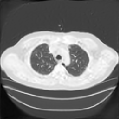

IV-F1 GeMix leads to more realistic images

One of our hypotheses is that GeMix is supposed to lead to more realistic images than traditional mixup or MMixup. Figure 2 illustrates a few examples produced by mixup (first column), MMixup (second column) and GeMix (third column). We observe that GeMix produces more anatomically coherent images, whereas the interpolation in pixel-space performed by mixup and MMixup leads to images that are not anatomically valid.